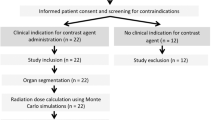

This study was performed in compliance with the Health Insurance Portability and Accountability Act (HIPAA), it was approved by the Institutional Review Board (IRB) at Massachusetts General Hospital, and informed consent waiver was obtained. The work involved retrospective analysis radiation dose records that patients received without any bearing on patient's diagnosis or treatment and there were no experiments on humans and/or the use of human tissue samples. The study included 8918 patients (4311 female; 4607 male; median age: 71.2 year old; min age: 21.6 year old; max age: 99.98 year old) who underwent multiple CT imaging exams over 5 years at a major tertiary care hospital in USA between 2013 and 2017 (Table 1). Patient’s age and sex distributions reflected the considered clinical scenario.

A dose monitoring system (Radimetrics, Bayer HealthCare, Leverkusen, Germany) provided patient information, age, sex, and scanner radiation output in terms of DLP11. The system also calculated with Monte Carlo methods organ doses (\({OD}_{T}\)) for 25 organs (\(T\)). Several metrics were calculated to perform the analysis (Table 2). The DLP-based effective dose (\({E}_{DLP}\)) was calculated multiplying the DLP by the anatomical region conversion factors for adult patients reported in Table A.2 of the ICRP publication 1021. Moreover, following the ICRP publication 103 tissue weighting factors, \({E}_{OD}\) was calculated per each patient6. The radiation risk index (\(RI\)) was estimated by applying the sex- and age- specific lifetime attributable risk of cancer incidence in the US population for the tissue \(T\) (\({r}_{T}\)) reported in BEIR VII to the patient-specific organ doses (\(OD_{T}\)): \(RI = \mathop \sum \limits_{T} r_{T} OD_{T}\)5,12,13. Lastly, the updated relative effective dose \({(E}_{r})\) was calculated adjusting \({E}_{OD}\) for an age and sex patient-specific factor \(f=\frac{RI}{{RI}_{rp}}\), where \({RI}_{rp}\) is the risk index calculated for a 35-year-old reference patient considering sex-averaged \({r}_{T}\) coefficients: \(E_{r} = f \times E_{OD}\)10. We tested the null hypotheses of no relationship between \({E}_{DLP}\), \({E}_{OD}\), and \({E}_{r}\), and \(RI\), each. For each metric, mean, median, range, and standard deviation were further calculated.